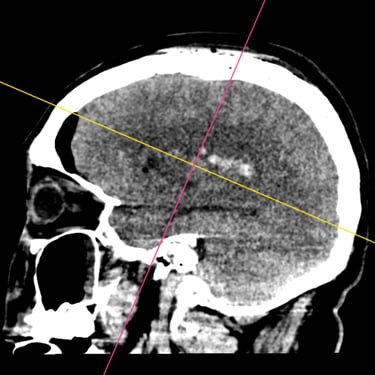

Hemorragia Intracerebral: Craneotomía y Evacuación del Hematoma

La hemorragia intracerebral es una emergencia neurológica grave que requiere diagnóstico rápido y tratamiento oportuno. Cuando el hematoma produce efecto de masa, deterioro del estado de conciencia o riesgo de herniación, la craneotomía y evacuación quirúrgica se convierten en la opción indicada. Este procedimiento permite abrir la bóveda craneal, retirar el coágulo y disminuir la presión intracraneal, preservando la función neurológica. Su objetivo es detener el daño secundario, mejorar la perfusión cerebral y estabilizar al paciente. La intervención temprana, combinada con cuidados críticos especializados, aumenta las posibilidades de supervivencia y recuperación funcional en este tipo de emergencia.